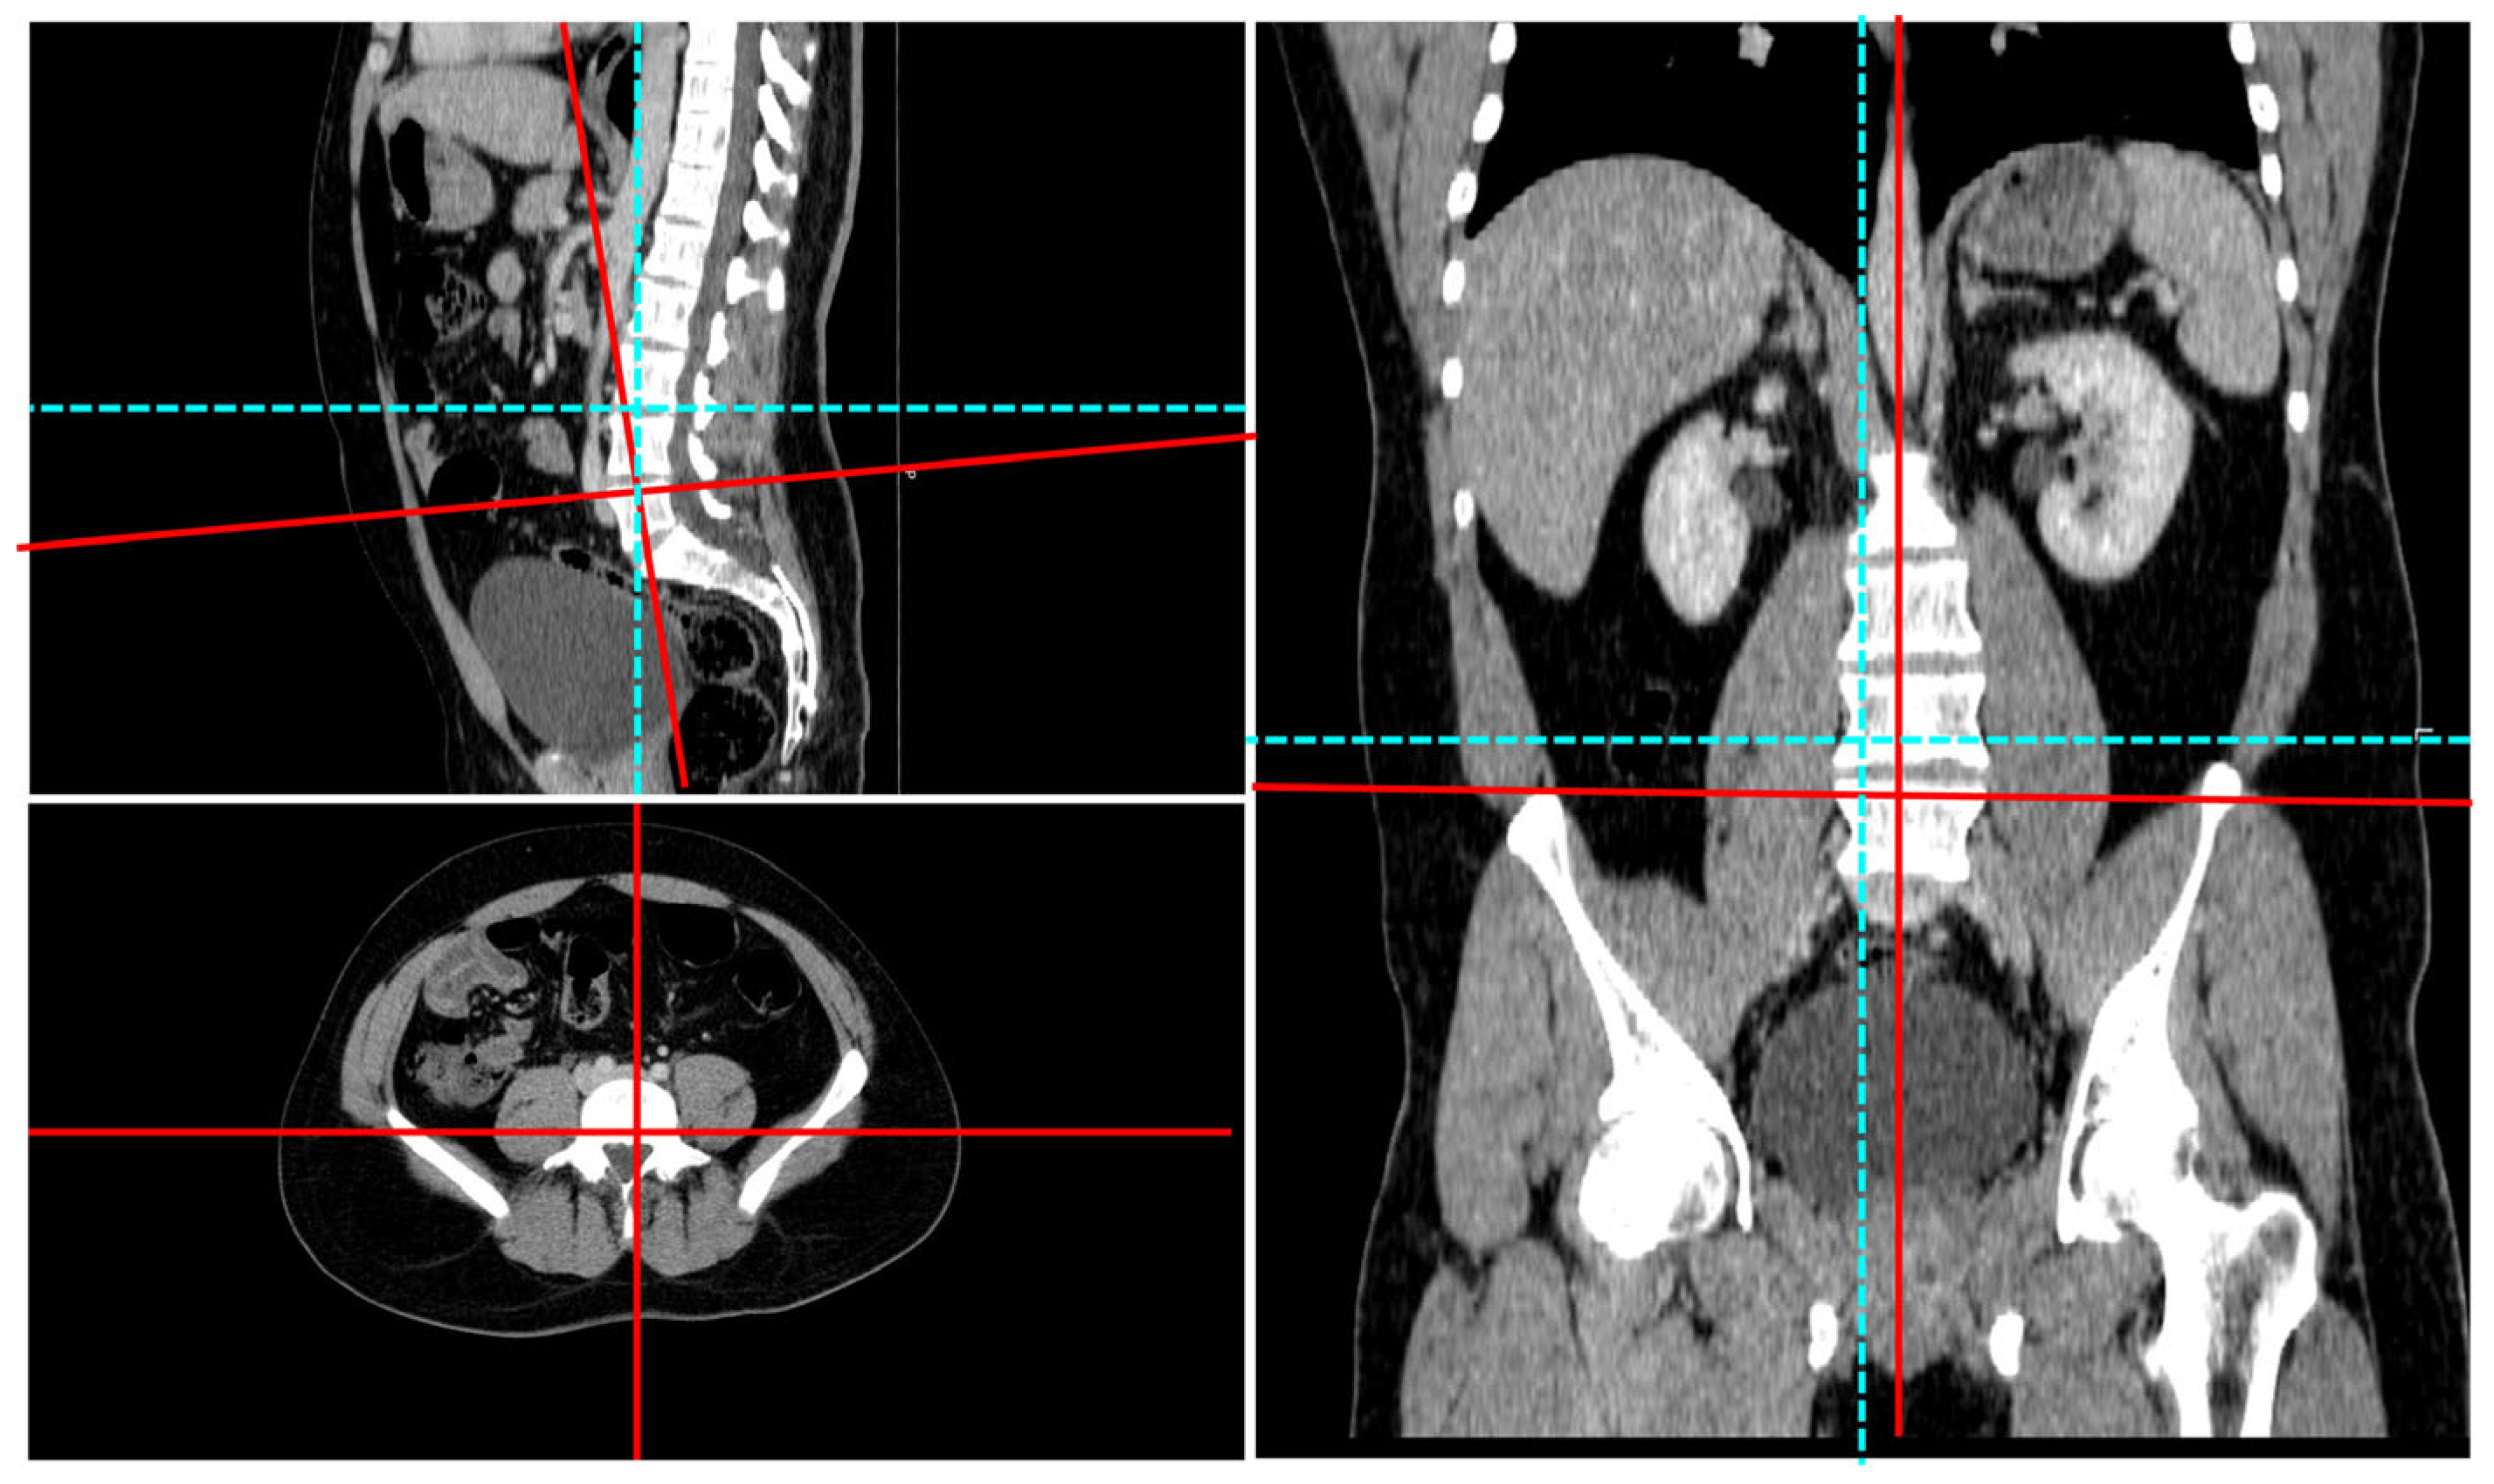

2.3. Radiologic Imaging